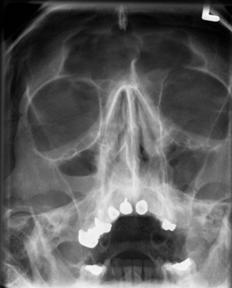

Las proyecciones que se suelen solicitar son la mentonasoplaca de Waters y el perfilograma (radiografía simple de huesos propios de la nariz)

Figura 35. Fractura nasal, nótese la deformidad, tumefacción y epistaxis. Figura 36. Radiografías (Rx) en fractura nasal. Rx izquierda (perfilograma) y Rx derecha (proyección de Waters)